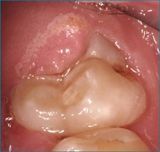

- Chirurgia mucogengivale

- Gengivectomia-gengivoplastica

Applicazioni Cliniche